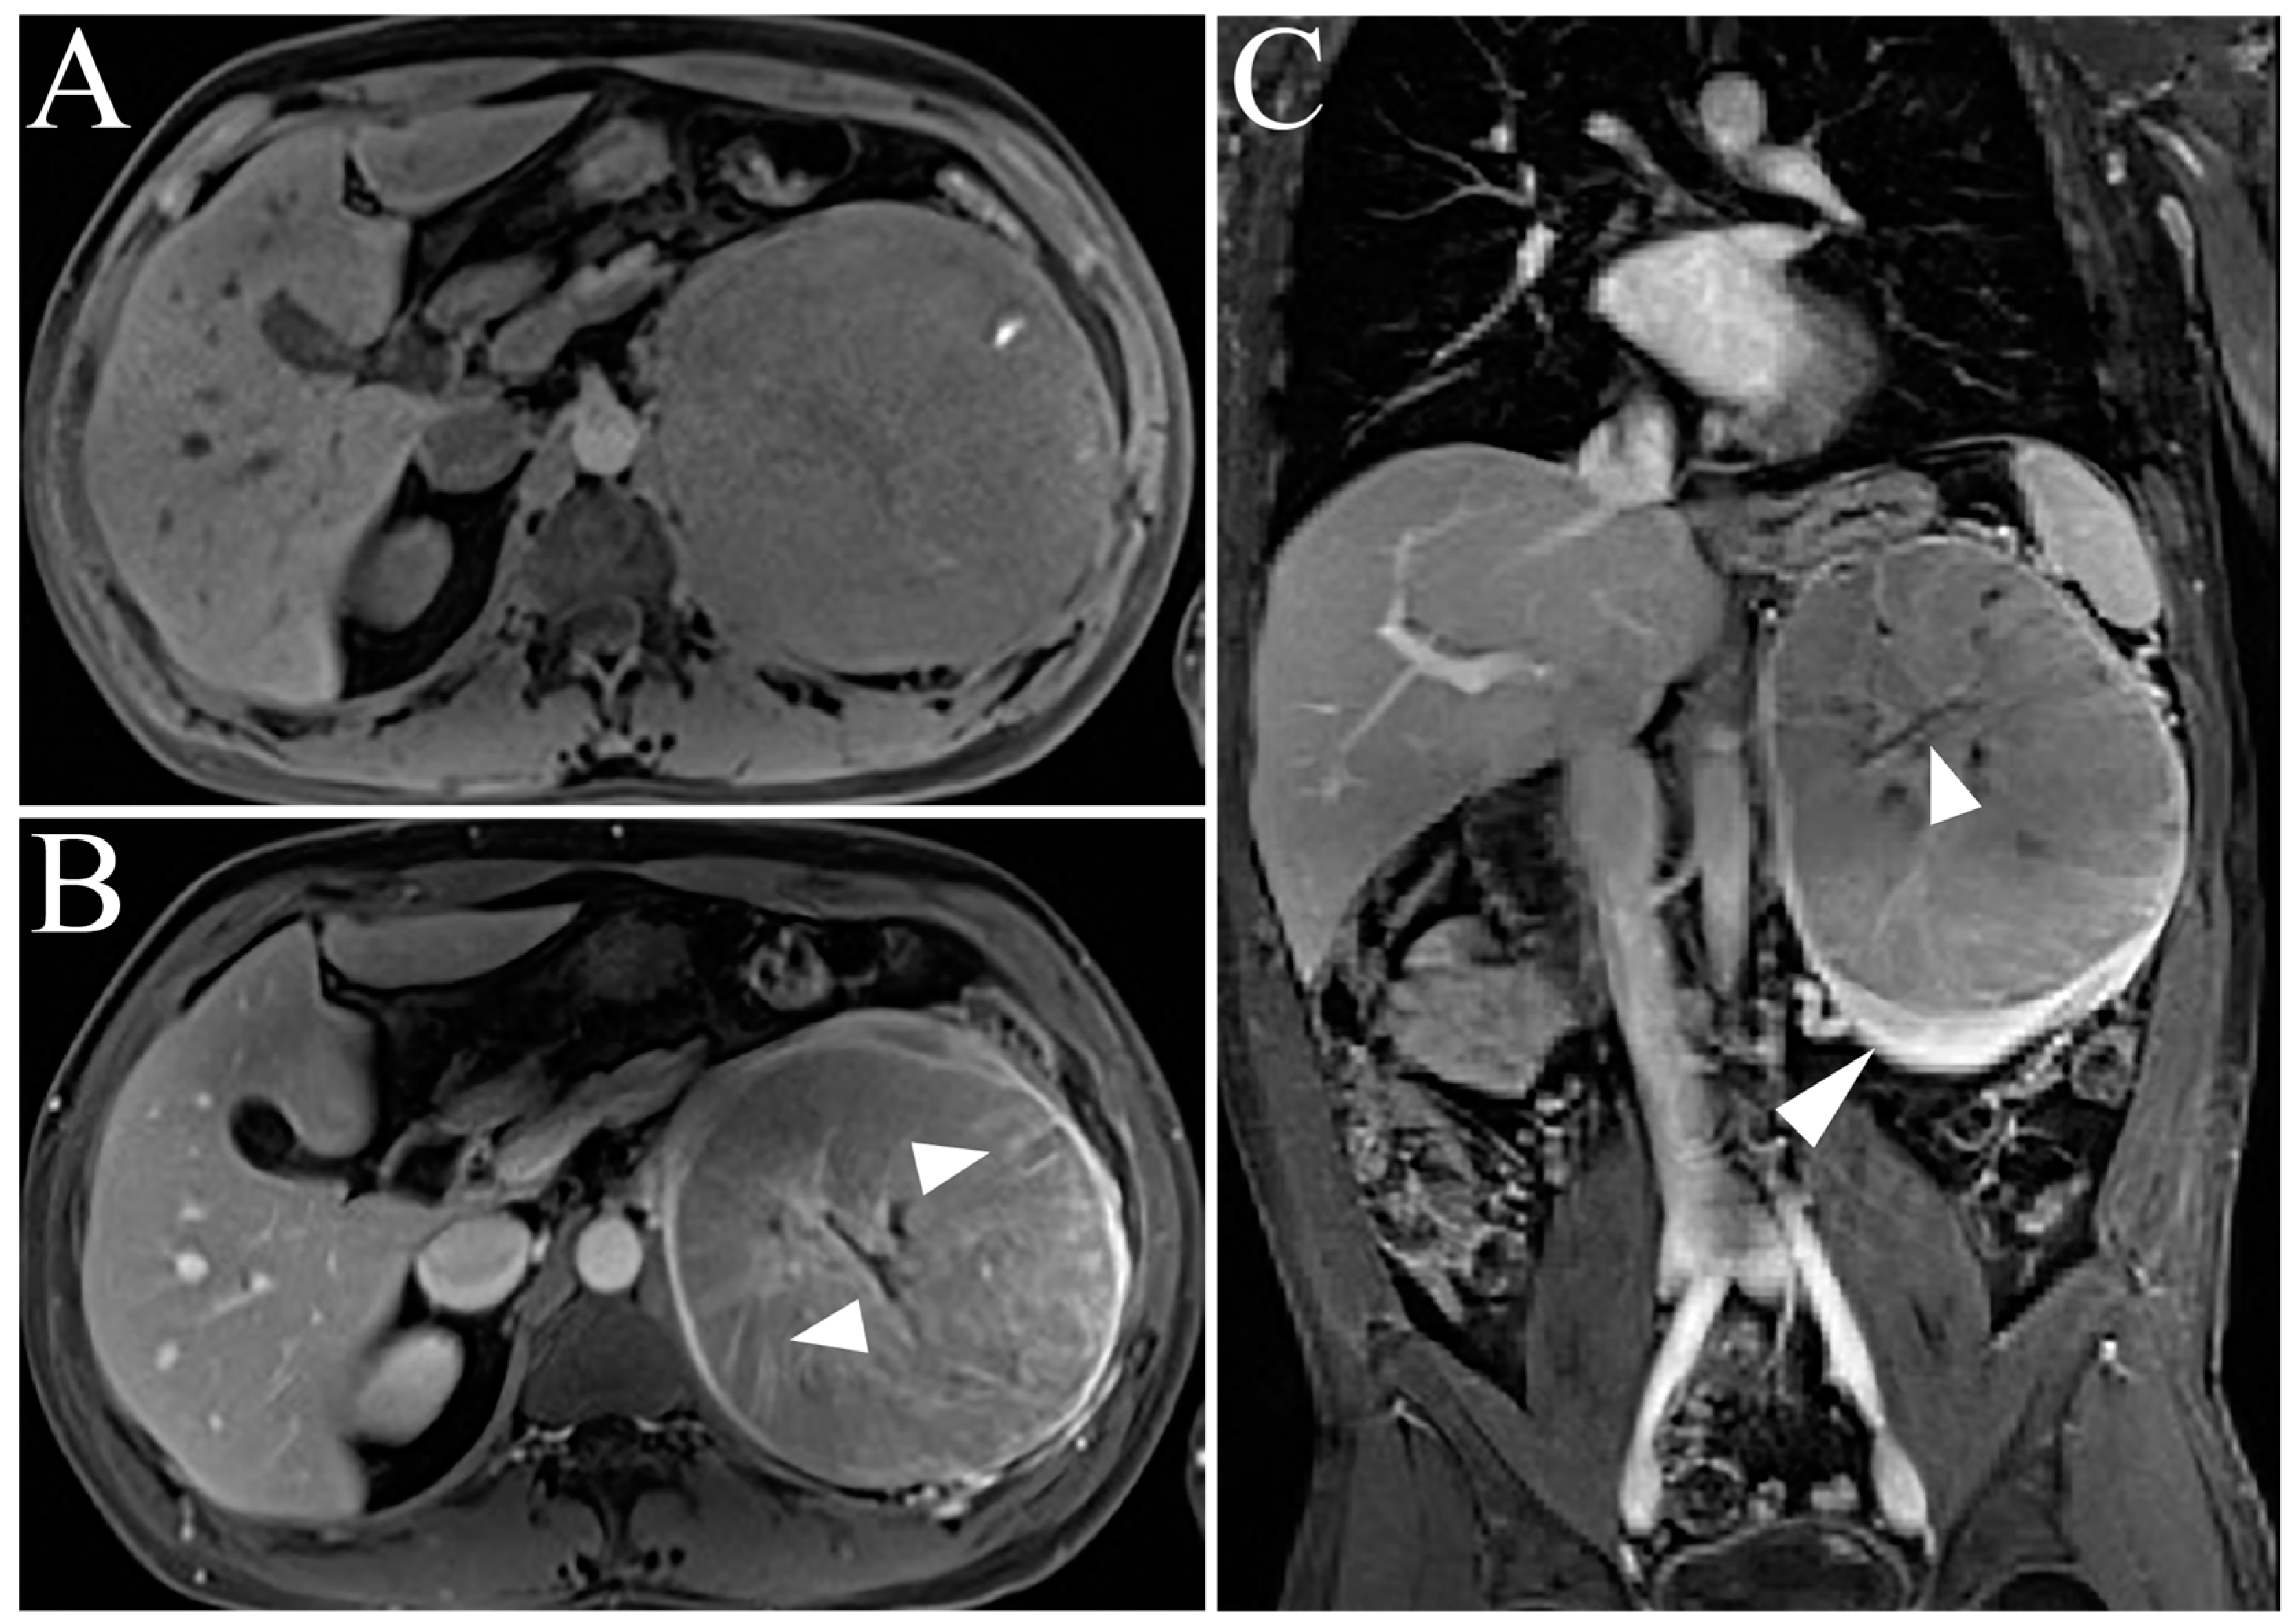

| Oncocytoma | T2-iso-to-hyperintense relative to normal parenchyma Central/eccentric T2-hyperintense scar Delayed enhancement of a central scar Segmental enhancement inversion pattern |

| Clear Cell RCC | Heterogenous, high T2-intensity Avid enhancement in corticomedullary and nephrogenic phases Microscopic fat as see on dual echo T1W in- and out-of-phase Invasion into surrounding vessels (esp. renal vein or IVC) Presence of necrosis or intralesional calcification |